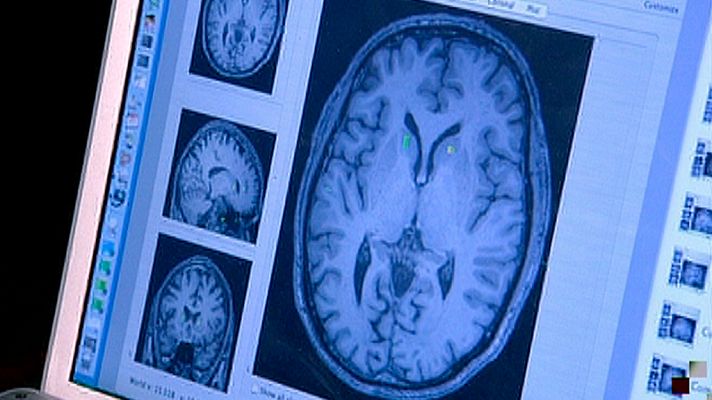

Gracias a una investigación llevada a cabo por el neurocientífico, Daniel Levitin junto con el cantante y compositor Sting, estamos más cerca de entender cómo trabaja el cerebro de un músico. Cómo se generan hormonas y conexiones neuronales que dan pie a la composición y la ejecución musical.